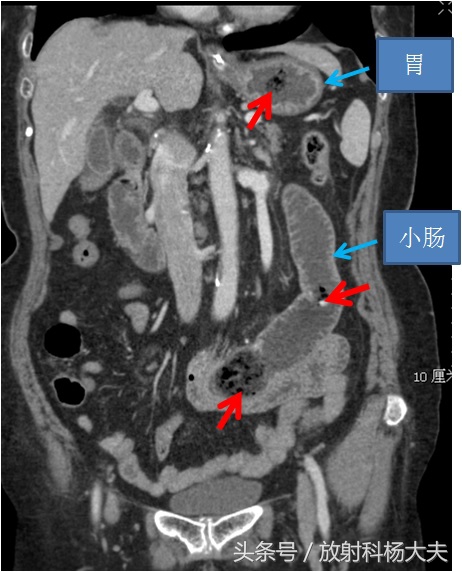

是的,吃下去的柿子在老人的胃里和小肠里形成了结石,叫柿石,属于植物性结石的范畴,柿子、山楂中果胶和单宁酸含量较高 ,遇到酸性较高的胃液可发生凝固沉淀而形成植物性结石。一般认为空腹时 食入多量柿子、山楂时引发植物性胃石机会更多。这种结石,跟常规理解的胆囊结石和肾结石等不同,看起来密度不高,而且里面含有气泡。如下图红箭所示。小肠里的柿石堵住了肠子,造成轻度梗阻的症状了。

在扩张与萎陷肠管移行区肠腔内见到含气泡的花斑样肿块是诊断柿石性小肠梗阻的特征性CT征象,CT检查应作为柿石症检查的最好的方法。小肠内出现这种表现,且有进食柿子病史者,应高度怀疑柿石。治疗方面,分内科保守治疗和外科治疗。内科保守治疗方面,胃内柿石相对容易,可以下胃镜碎石,配合一些碱*药性**物等,小肠的因为位置太深,相对麻烦,多采用禁食、胃肠减压、通便、营养支持等治疗。严重者需要手术,包括腹腔镜手术及开放手术。外科手术仍是比较有效的解决柿石性肠梗阻的方法。